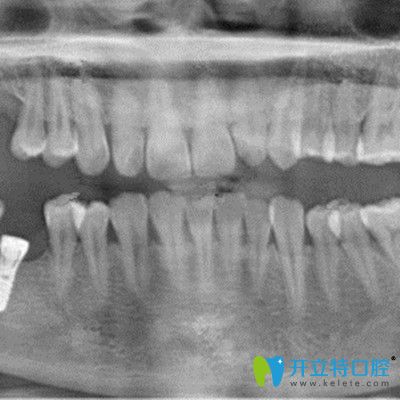

再次到,譚醫(yī)生表示我的牙骨質條件還是挺好的,當天就做了手術,裝入了種植體,戴了臨時冠,整個手術過程大概持續(xù)了一個小時左右。因為做的是微創(chuàng)即可種植技術,所以基本沒有痛感。

手術有3個月了,今天過來復診,譚醫(yī)生告知檢查結果顯示我的牙槽骨愈合的較好,當天就更我裝了種植牙的牙冠,現在我感覺跟真牙基本沒有區(qū)別,吃東西也完全不受影響了。